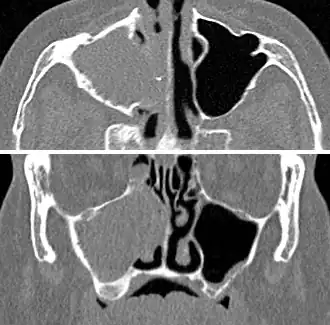

For cases of maxillary sinusitis, limited field CBCT imaging, as compared to periapical radiographs, improves the ability to detect the teeth as the sources for sinusitis. A coronal CT picture may also be useful.[60]

Chronic

For sinusitis lasting more than 12 weeks, a CT scan is recommended.[66] On a CT scan, acute sinus secretions have a radiodensity of 10 to 25 Hounsfield units (HU). In a more chronic state, they become more viscous, with a radiodensity of 30 to 60 HU.[69]

-

CT of chronic sinusitis -

CT scan of chronic sinusitis, showing a filled right maxillary sinus with sclerotic thickened bone -